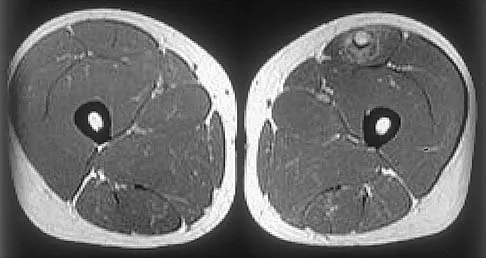

Figure 16 shows an axial MRI scan through the knee joint. What structure is identified by the arrow?

Explanation